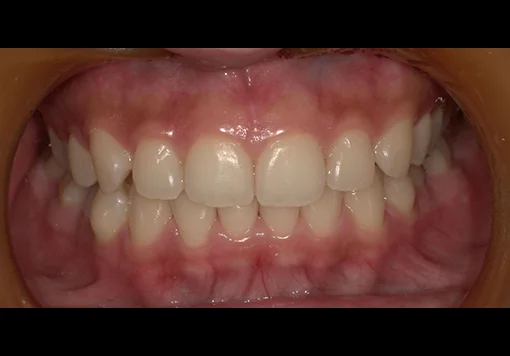

Case 04

before

after

- 主訴:前歯のガタつき・上下の歯並びの不均一を改善したい。

根管治療途中の歯を治したい - 治療内容:マウスピース型矯正装置(SureSmile)による全顎矯正。

下顎1本インプラント埋入 - 治療期間:約36ヶ月

- 診断結果:

・上下顎に叢生を認め、特に上顎前歯部の位置不良が強い状態。

・噛み合わせのズレがあり、審美性・機能性の改善が必要と判断。

・抜歯を伴わないマウスピース矯正での改善が可能と診断。

歯根破折 - 治療後経過:

・前歯部の配列が整い、正中・噛み合わせが改善。経過も良好。 - 治療費用:マウスピース矯正(SureSmile):88万円税込

インプラント45万円税込

※症例により費用は前後します。